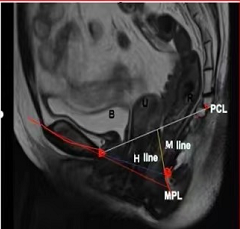

1. 耻尾线(PCL):正中位上耻骨联合下缘至尾骨关节最后一个关节或者倒数第二个关节,代表正常盆底。

2.耻骨中轴线(MPL):贯穿耻骨联合长轴的线,代表处女膜水平。

3.H线:从耻骨联合下缘至ARJ的连线,反映肛提肌裂孔前后径,正常长度<6cm,大于6cm代表肛提肌裂孔扩大。

4.M线:从PCL线至ARJ的垂直距离,代表盆底下降幅度,正常长度≤5cm,大于2cm认为肛提肌裂孔下移。